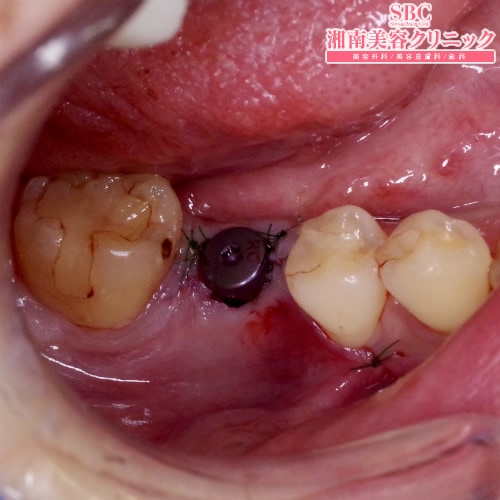

術前は抜けてしまった奥歯。この部分にインプラントを埋入。キャップをねじ止めした状態です。最終的にはこのキャップを土台に置き換えて、その上にセラミックを装着します。

術前は抜けてしまった奥歯。

この部分にインプラントを埋入。キャップをねじ止めした状態です。

最終的にはこのキャップを土台に置き換えて、その上にセラミックを装着します。